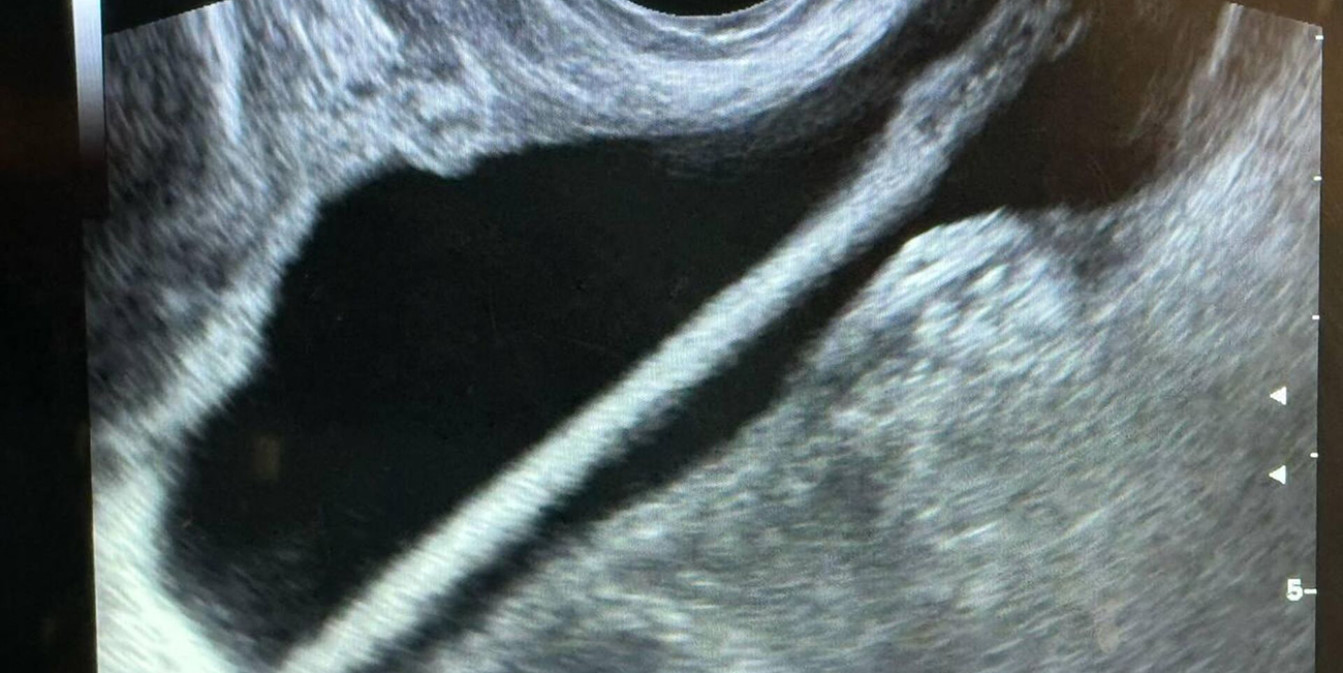

В Подмосковье врачи удалили из мочевого пузыря женщины карандаш

В Красногорской больнице врачи оказали помощь 46‑летней пациентке, у которой в мочевом пузыре оказался косметический карандаш. Женщина самостоятельно ввела предмет в мочеиспускательный канал, после чего обратилась за медицинской помощью, сообщили в Минздраве Московской области.

Пациентку госпитализировали в урологическое отделение. Сначала ей провели УЗИ, затем врачи с помощью эндоскопа удалили инородное тело. Операция прошла успешно, осложнений не возникло.

Фото: Министерство здравоохранения Московской области